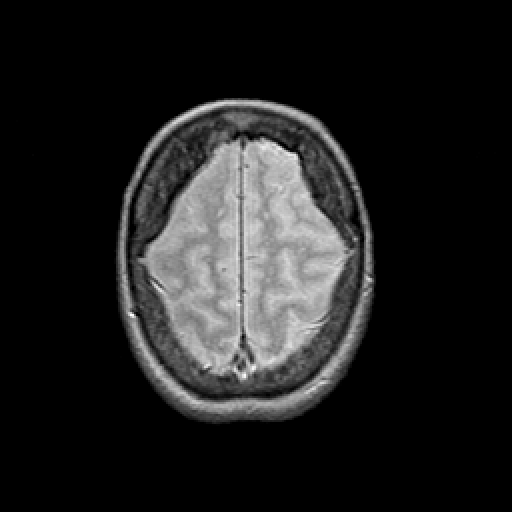

Proton density-weighted structural MR: Slice 44

Slice 44